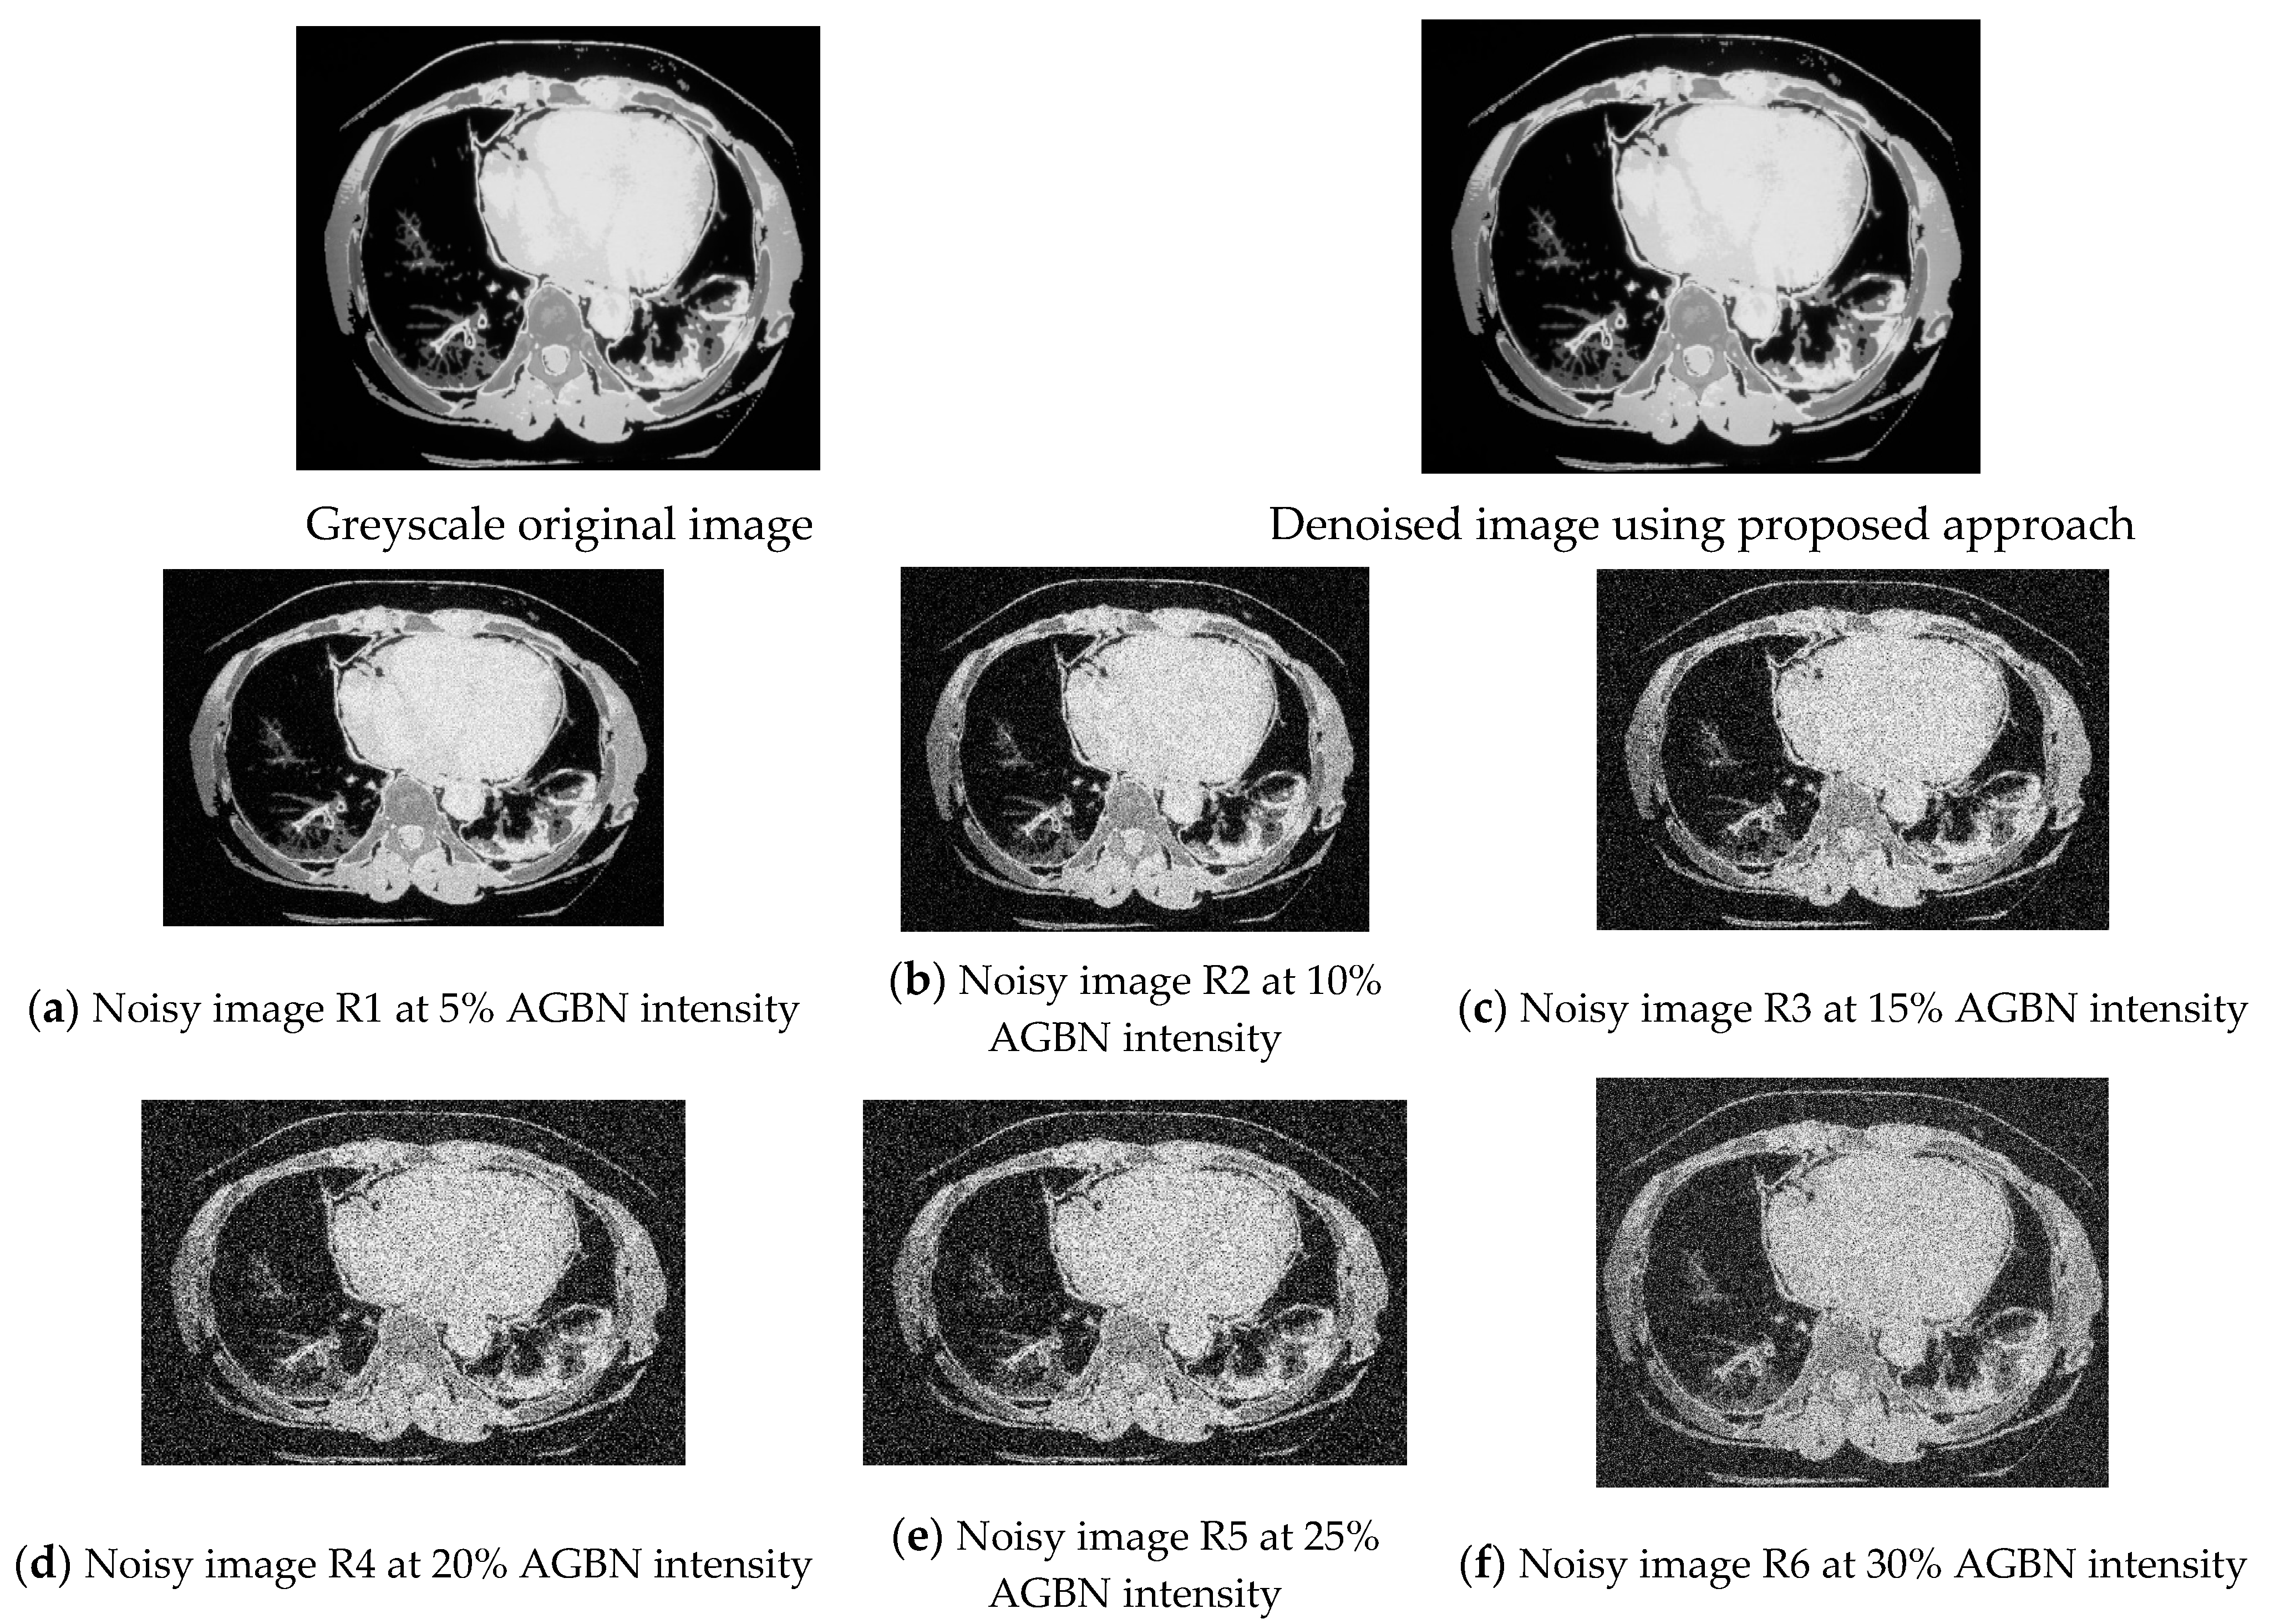

In Figure 3, the CT scan image was corrupted by adding a 5–30% Gaussian blur noise level. The addition of noise was necessary to obtain the measure of error margins when noise levels deviated. The focus was on reducing the AGBN, which had 1096 images, translating to 85% noisy images contaminated with AGBN. Figure 3 shows the original greyscale CT scan image and the denoised image using the proposed approach. Images R1 to R6 had Gaussian blur noise added at different noise intensities to allow for testing the denoising method’s effectiveness under various noise levels, as shown in Figure 3.

Figure 3.

CT scan images with added Gaussian blur noise at 5% to 30% noise intensities in figure (a–f).

The noisy images were denoised using wiener, mean, median, DWT, Gaussian, non-local means (NLM) filter, and DnCNN for selected CT scan images at various additive Gaussian blur noise (GBN) intensities (5–30% noise intensity) as shown in Figure 3a–f. As more noise is added to the image, blurring and visual quality increases. Image denoising techniques aim to improve the visual quality and interpretability of images by reducing the impact of noise which can otherwise degrade image quality and hinder the ability to extract meaningful information from the image. It was demonstrated that the proposed approach of wavelet–anisotropic Gaussian filter-based denoising CNN remarkably reduced the additive GBN, and at the same time, minimized the blurring effect and improved visual quality, achieving better image and fine details’ preservation compared to other schemes used in the experiment.